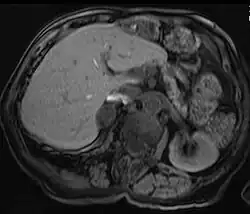

| Adrenal adenoma in a patient with Conn syndrome | |

Diagnosis

Due to their asymptomatic nature, most reported cases of adrenal adenomas have been discerned fortuitously through autopsy, or during medical imaging, particularly CT scan (computed tomography) and magnetic resonance imaging. Hence, they have earned the title incidentaloma referring to small adenoma discovered incidentally.[9] Though adrenocortical adenomas are considered challenging to differentiate from the normal adrenal cortex, they appear as well-circumscribed lesions once isolated.

Imaging Diagnostics

Adrenal-dedicated CT and MRI imaging can be performed to distinguish benign adenomas from potentially malignant lesions.[10] Online calculators assist radiologists in calculating the washout of contrast in adrenal nodules on CT[11] and chemical shift on MRI[12].